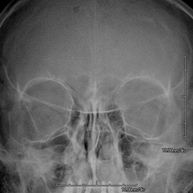

Técnica mediante la cual, utilizando rayos X, se obtienen imágenes del cráneo para su estudio. Indicaciones: traumatismo, cierre precoz de suturas craneales. - RX Senos Paranasales

Técnica mediante la cual, utilizando rayos X, se obtienen imágenes de los senos paranasales para su estudio. Indicaciones: dificultad respiratoria nasal, tos crónica, cefalea, mucosidad. - RX ATM (Articulación Temporo-Mandibular)

Técnica mediante la cual, utilizando rayos X, se obtienen imágenes del conducto auditivo interno para su estudio. Indicaciones: pérdida de la audición. - RX Orbitas

Técnica mediante la cual, utilizando rayos X, se obtienen imágenes de las órbitas para su estudio. Indicaciones: cuerpo extraño ocular, traumatismo, infecciones. - RX Mandibular